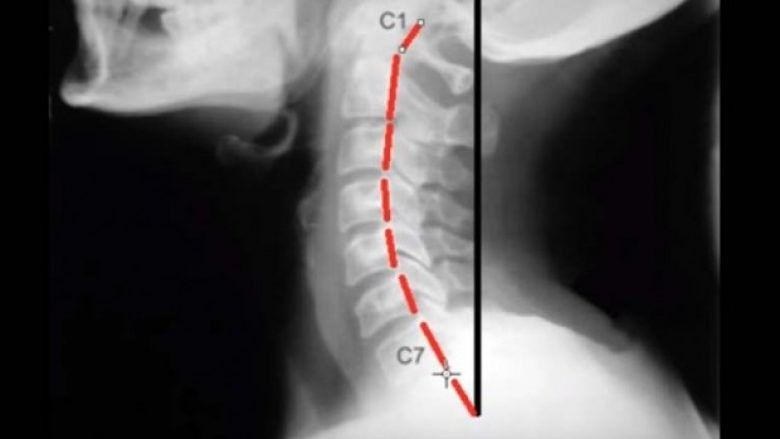

Në spotin e ardhshëm mund të shihni se si duket incizimi i qafës e cila rri drejt, përkatësisht pozitën natyrore të unazave.

Ndërkaq këtu shihet pozita e unazave kur qafa është e lëshuar, gjë që me ushtrimet paraprake dëshirojmë t’i shmangim.